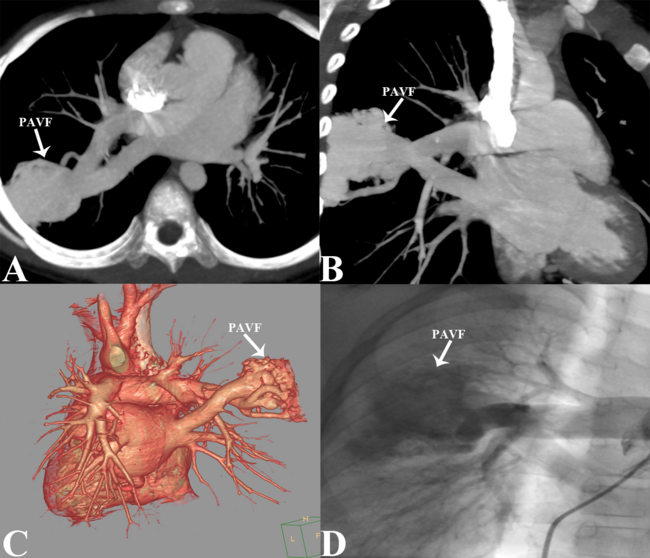

Maximal intensity projection computed tomography angiography (CTA) revealed a giant PAVF between the right inferior pulmonary artery and the right inferior pulmonary vein, measuring 6.8 × 5.4 cm (Figure A, B). Volume-rendered CTA showed the feeding and draining vessels of the PAVF (Figure C). Selective right pulmonary angiography revealed the giant PAVF (Figure D, Video 1).